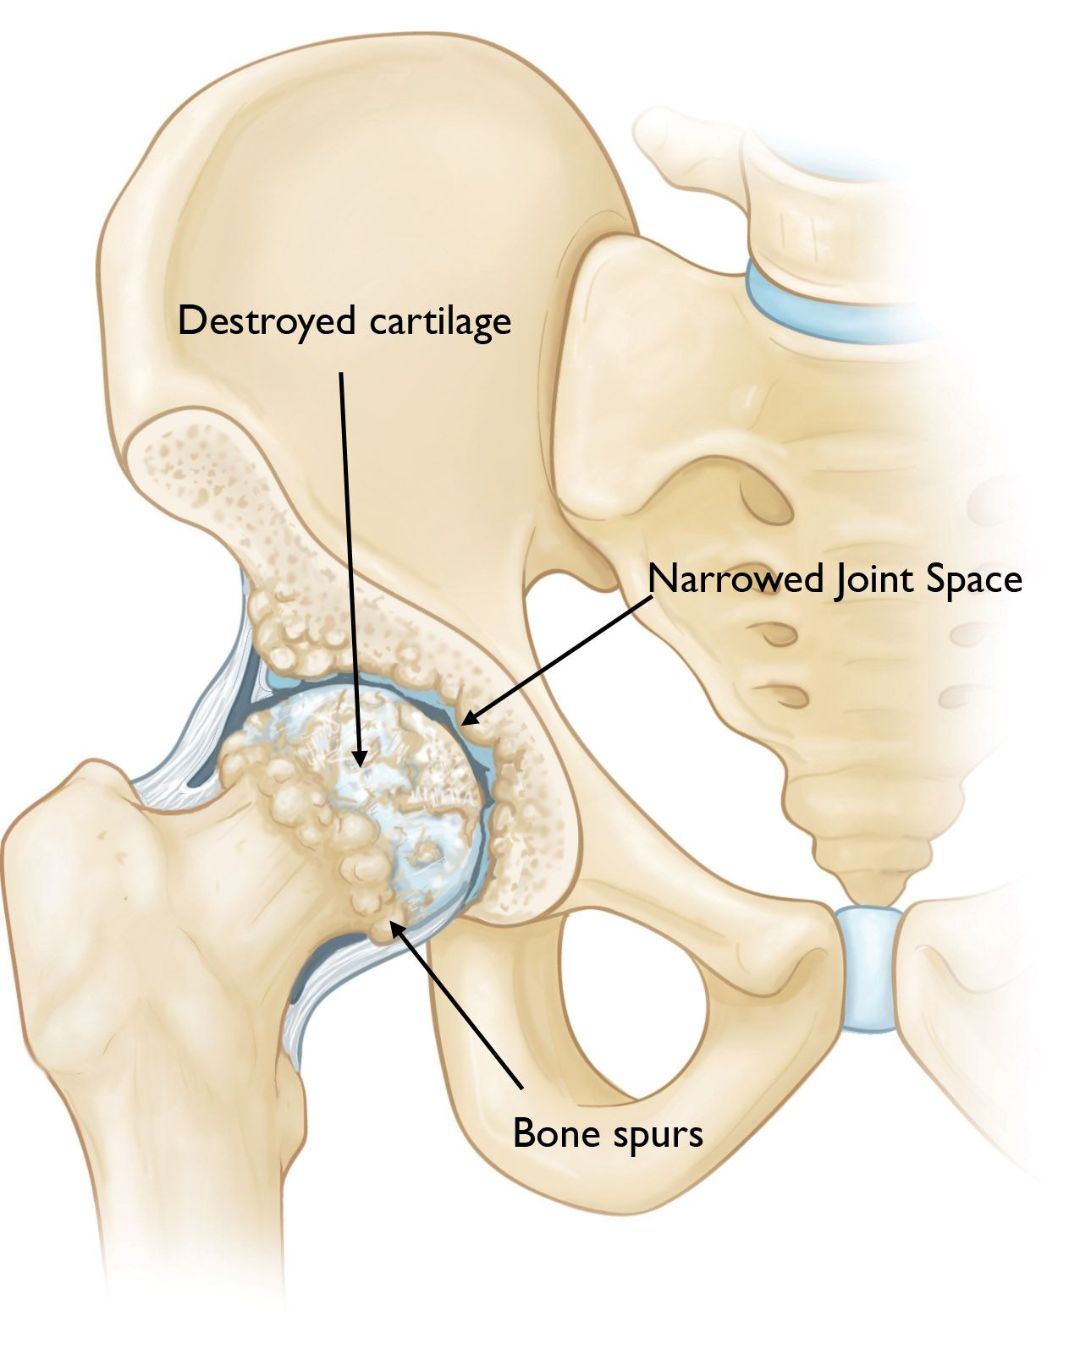

Osteoarthritis of the hip

Rheumatoid arthritis

Severe hip stiffness and deformity